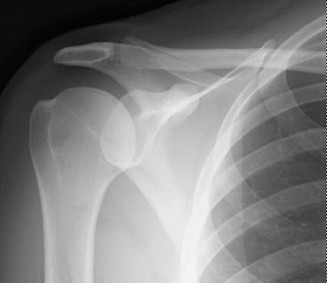

Radiographic Evaluation and Templating

Standard radiographic evaluation includes an anteroposterior (AP) view of the clavicle and a 15 to 20 degree cephalic tilt view. The cephalic tilt view projects the clavicle free from the underlying ribs and provides a more accurate assessment of superior-inferior displacement and shortening. In cases of severe comminution, marked displacement, or suspected intra-articular extension into the sternoclavicular or acromioclavicular joints, a computed tomography (CT) scan with 3D reconstructions is highly recommended. CT imaging provides precise characterization of butterfly fragments and aids in determining the appropriate length and contour of the fixation construct.